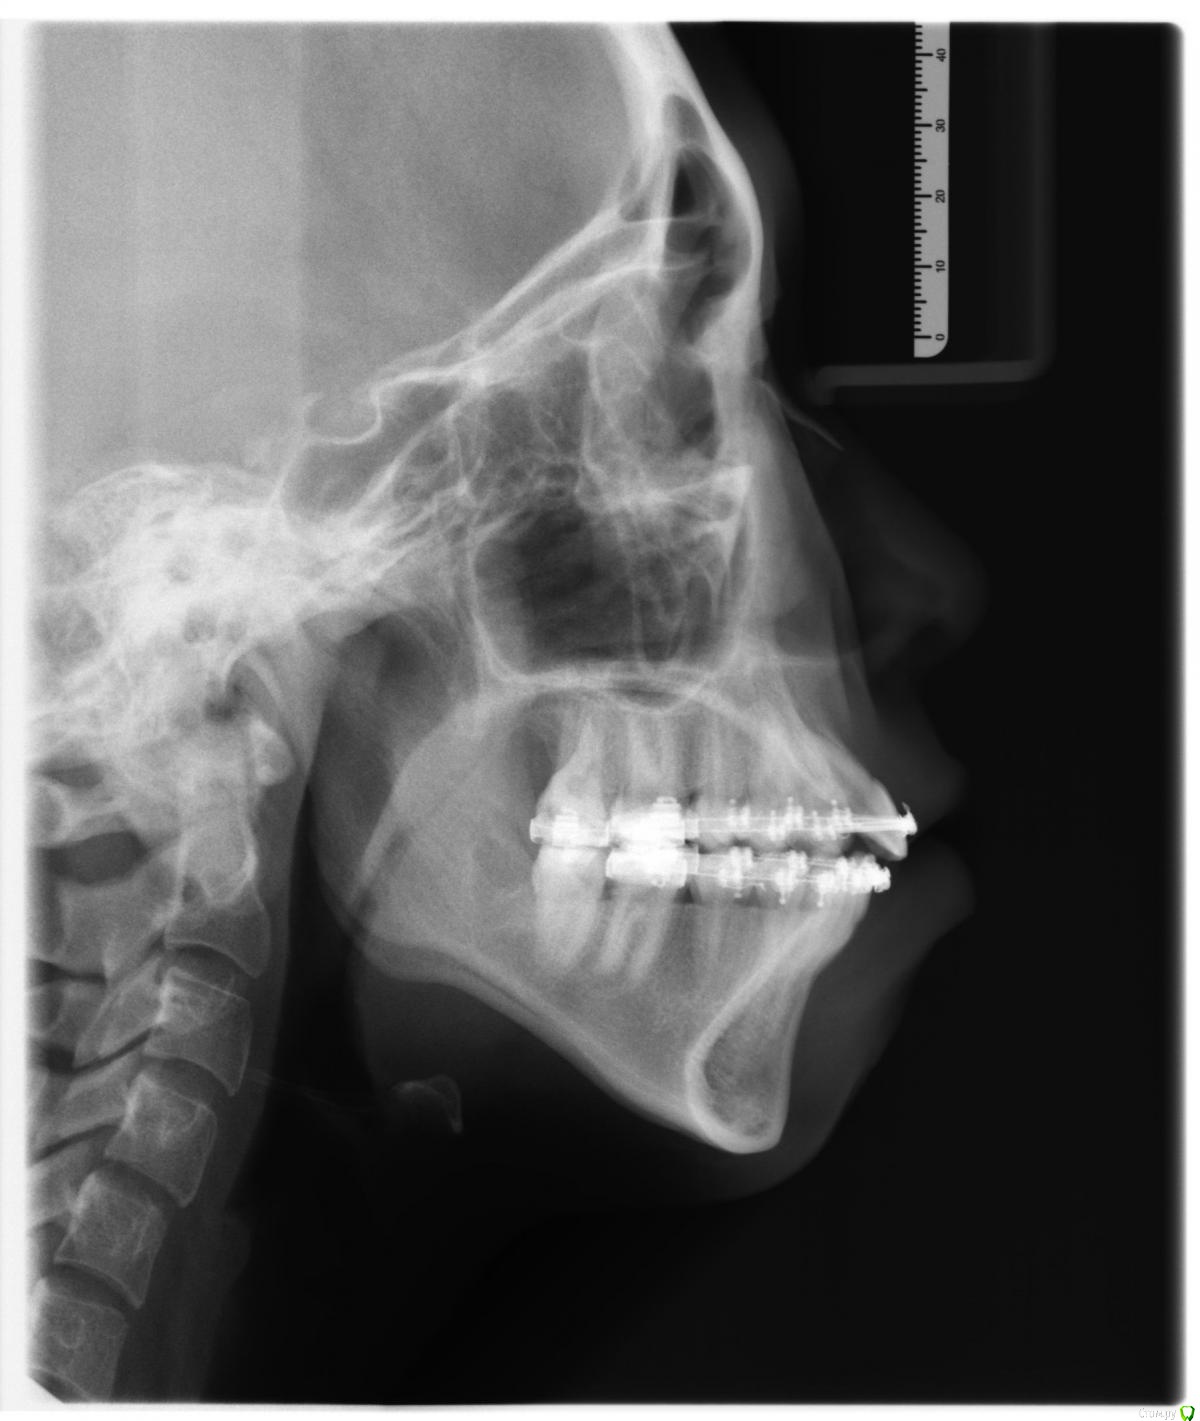

Амина Опубликовано 4 июня, 2016 Автор Поделиться Опубликовано 4 июня, 2016 (изменено) Здравствуйте. Мне очень нужен совет. Дочке 12 лет. Повели к стоматологу потому что зубки местами несколько неровные. Не критично, но всё же девочка же. В процессе выяснилось, что:1) у ребенка неправильный прикус. Норма - нижние зубы за верхними. Бывает, что нижние перед верхними. А у неё нижний и верхний ряд зубов ровненько на одной линии. В общем сказали, что надо ставить брекеты обязательно - исправлять кривизну зубов и неправильный прикус.2) у дочки нет двух верхних передних резцов. То есть у всех впереди вверху посерединке четыре резца и затем по бокам идут клыки. А у неё два резца и следом клыки по бокам. На снимке (панорамная съемка) видно, что нет даже зачатков вторых резцов. Врач говорит, что выхода два1) раздвинуть с помощью брекетов зубы увеличив расстояние между резцами и клыками. Затем ребенок лет до 18-ти должен ходить с какой-то чуть ли не вставной челюстью. После чего ей поставят имплантанты2) сдвинуть зубы чтобы между ними не было большого расстояния и затем (попозже) подпилить клыки.Нужно это для того, чтобы в зрелом возрасте из-за отсутствия двух резцов у дочери не было больших зазоров между зубами.Мне первый вариант не нравится категорически (вставные челюсти, имплантанты - зачем так ребенка мучить). Насчет второго - не слишком устраивает подпиливание. Врач также говорит, что отсутствие этих зубов не аномалия какая-то, сейчас многие дети такие. Посоветуйте, что нам делать. Заранее спасибо! Прошу прощения за корявое изложение - не владею специальными терминами. в 2009 году была такая история. но в итоге мы пошли по первому варианту снимок 2015 года Изменено 4 июня, 2016 пользователем Амина Ссылка на комментарий

Амина Опубликовано 4 июня, 2016 Автор Поделиться Опубликовано 4 июня, 2016 вот снимок 2016 года Ссылка на комментарий

Амина Опубликовано 4 июня, 2016 Автор Поделиться Опубликовано 4 июня, 2016 Это снимок 2015 года Ссылка на комментарий